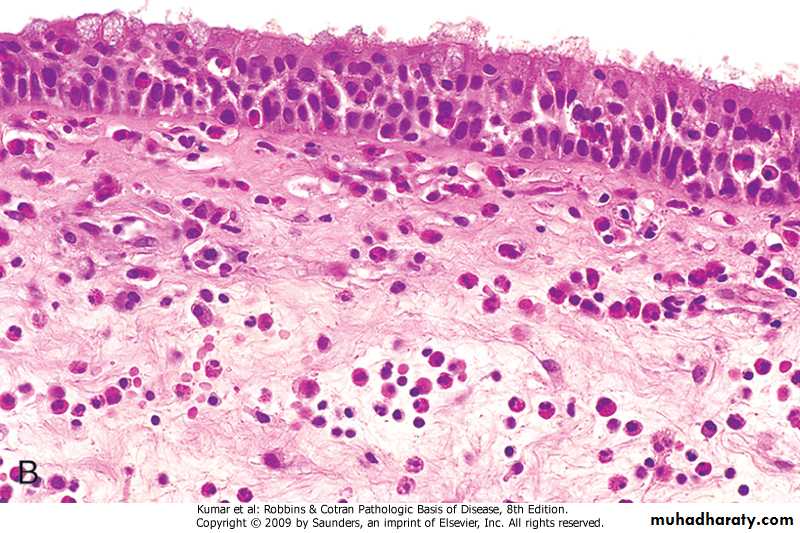

Bronchial Asthma : Pathology

Gross: The lung are overinflated

Microscopical:

1.The lumen of the bronchi and bronchiole contain thick mucus plug (containing whorls of epithelium called curschmann spirals),charcot leyden crystals and eosinophils

2. The basement membrane shows characteristic hyaline thickening

3. The submucosa shows congestion . edema and infiltration by eosinophils & mast cells

4. The bronchial muscle are hypertrophied